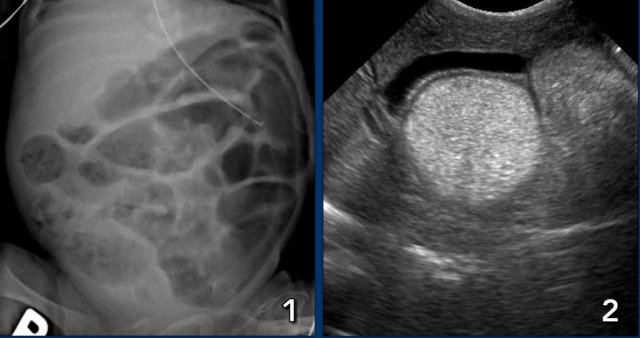

Images

Radiograph of a 2 month old baby with bilious vomiting after diaphragmatic hernia operation. There is very little bowel air consistent with the vomiting and collapsed bowel. On ultrasound ascites and a distended bowel loop with decreased perfusion are seen. In the mesentery a twist of the vessels is seen consistent with volvulus.